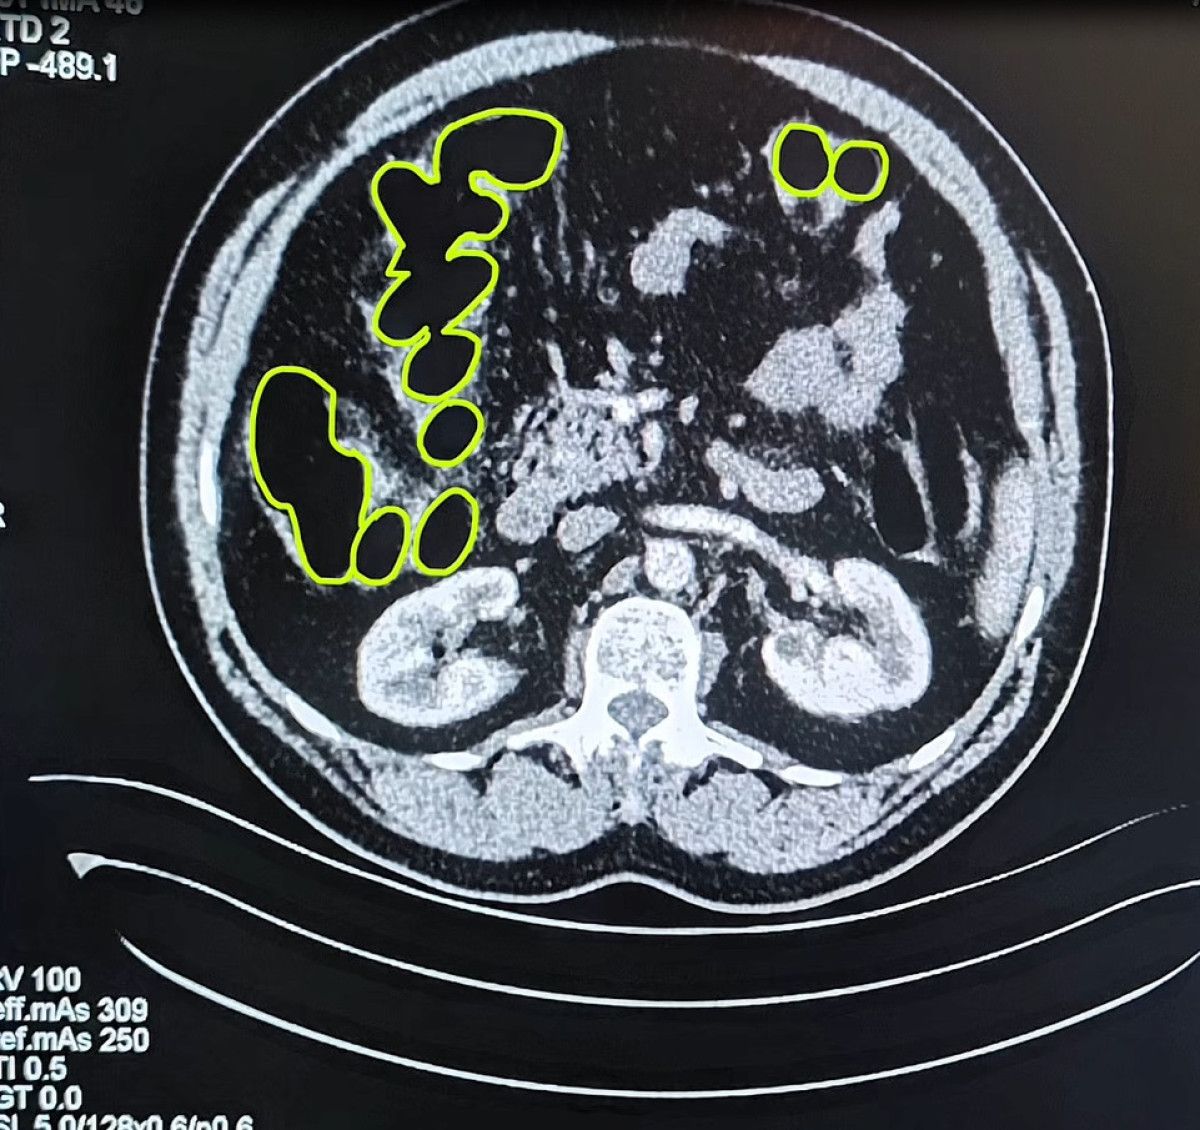

Kayseri Vilayet Jandarma Komutanlığı grupları Kocasinan ilçesi Himmetdede Mahallesi’nde İran asıllı 3 şüphelinin bulunduğu ticari aracı durdurdu.

Araçtaki A.O. (51), M.S. (37) ve P.S.’nin (28) üzerinde yapılan aramada bir ölçü uyuşturucu bulundu.

Zanlıların uyuşturucu unsurları yutmuş olabileceğini kıymetlendiren gruplar bu bireyleri hastaneye götürdü.

MİDELERİNDEN UYUŞTURUCU ÇIKTI

Röntgenlerinde midelerinde uyuşturucu unsur olduğu belirlenen zanlılardan 20 gram çeşitli uyuşturucu unsur ile 117 uyuşturucu hap ele geçirildi.